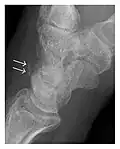

Figure 3: A 26-year-old man presenting with wrist pain after being assaulted. (a) Initial anteroposterior radiograph shows a subtle linear lucency within the scaphoid extending to the scaphocapitate articular surface that was overlooked (arrow). (b) Initial "scaphoid" view was negative. (c) Followup anteroposterior radiographs, 12 days later, shows obvious scaphoid fracture (arrows).[1]

Triquetral fracture usually occurs on the dorsal aspect by impingement from the ulnar styloid or avulsion of strong ligamentous attachment. The dorsal avulsion fracture or "chip fracture" appears as a small bony fragment on the dorsal aspect of the triquetrum and is best detected on the lateral view(Figure 4). When radiography is negative in patients with high suspicion of a fracture, both MRI and MDCT will be of value. However, it has been shown that MRI is superior for detecting trabecular fractures in carpal bones.